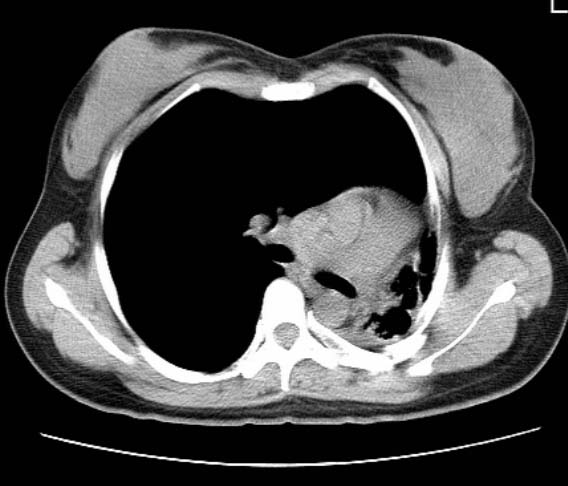

标题: CT25648:求教:是肺发育不全还是结核?

女  20岁。一月前咳血,诊“肺结核”抗痨治疗一月后,咳血停止,现复查。病人精神好。前后ct片对比未见明显变化。既往体检“正常”

1)考虑左肺结核并肺不张、支气管扩张。2)纵隔疝。

考虑左肺结核,左肺毁损,纵膈左偏,既往体检正常不可靠,tb一个月也不会这个样子的,有钙化,应该病程较长,冰冻三尺非一日之寒!

左肺发育不全。

考虑左肺结核,左肺毁损,纵膈左偏,既往体检正常不可靠,tb一个月也不会这个样子的,有钙化,应该病程较长,冰冻三尺非一日之寒

结核,左肺毁损。